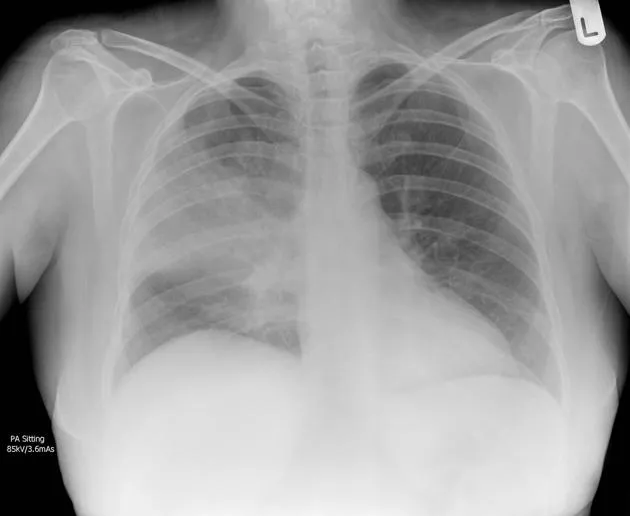

| Respiratory | ARDS development | Hypoxemia, infiltrates | P/F ratio <200 | 30-50% increase |

| CURB-65 | Pneumonia severity | 80-85% | 75-80% | 3 minutes | Admission decisions |